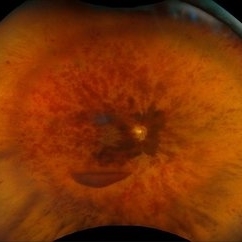

Suprachoroidal Hemorrhage

Suprachoroidal Hemorrhage

Aug 4 2025 by Anjana Mirajkar, MS Ophthalmology

A fundus photograph of a 56 year old female with a 360 degree suprachoroidal hemorrhage with a 360 degree crumpled retina during cataract surgery.

Photographer: Dr. Anjana Mirajkar- HV Desai eye hospital ,Pune

Imaging device: optos

Condition/keywords: giant retinal tear, suprachoroidal hemorrhage